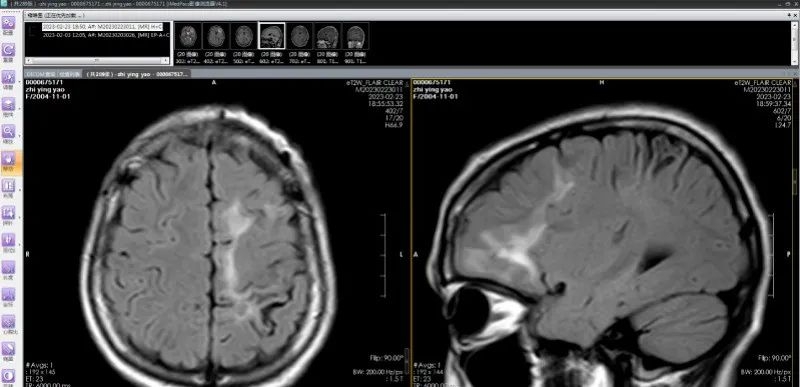

脑软化灶实为虫体在颅内的爬行轨迹;(左)从下往上移动,(右)从后往前移动

经过系列相关检查,发现彤彤左侧额叶存在多发病变,且两次发作症状不尽相同,怀疑是寄生虫感染。进一步检查结果提示:裂头蚴IgG抗体阳性;视频脑电图显示:左侧额顶叶多发放电。

多发脑软化灶实为虫体在颅内爬行产生的损伤,患者癫痫发作的根源在于寄生虫对大脑的炎性刺激,造成大脑异常放电。